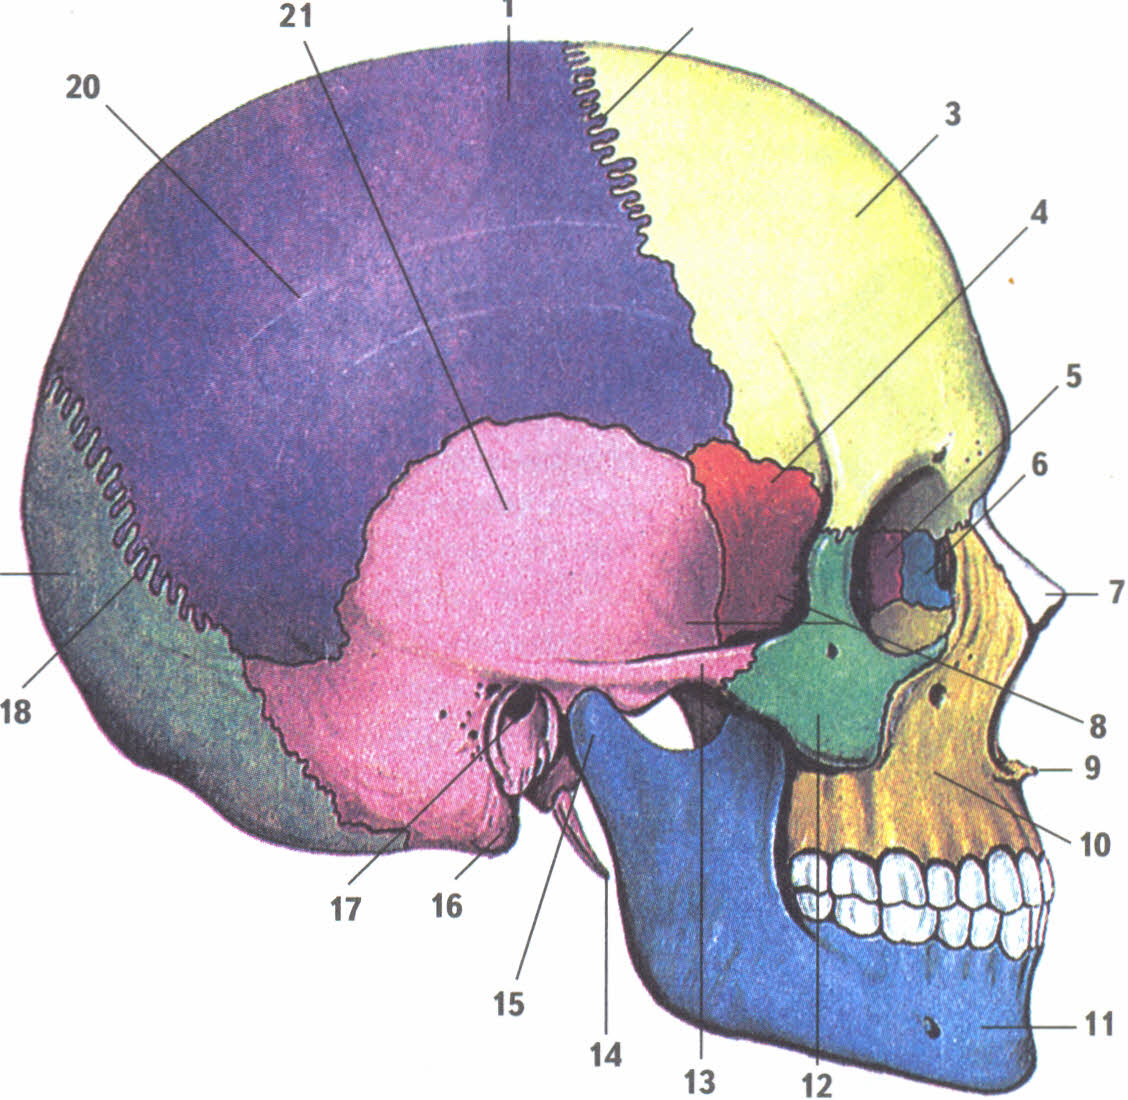

Анатомические изображения срединной сагиттальной линии черепа